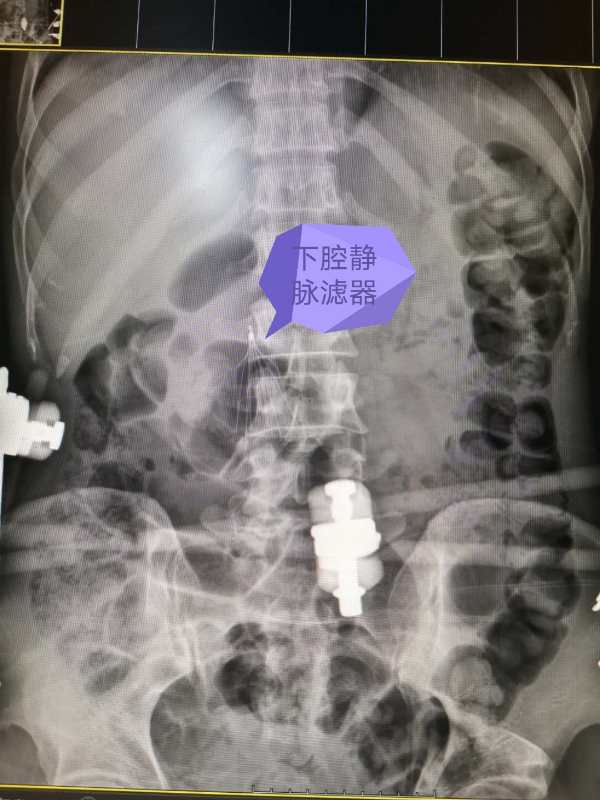

MDT惠及醫(yī)聯(lián)體 技術(shù)下沉顯奇功——柳州市人民醫(yī)院血管外科聯(lián)合超聲科在鹿寨縣人民醫(yī)院成功開展經(jīng)超聲引導下下腔靜脈濾器植入術(shù)

經(jīng)過仔細評估和檢查后手術(shù)開始,在張煒副主任超聲低頻探頭全程引導下,陳俞宏主任醫(yī)師通過超聲屏幕實時觀察血管管壁、管腔情況及周圍結(jié)構(gòu),測量下腔靜脈中下段橫徑和前后徑,了解腎靜脈位置,很快明確了濾器放置位置,同時運用其嫻熟的技巧快速穿刺成功,靈活的指尖讓輸送導管在血管通路內(nèi)順利前行,僅半個小時就成功地將濾器釋放在下腔靜脈預定位置,術(shù)后腹部平片顯示濾器打開良好,位置準確,患者次日順利完成后續(xù)骨科手術(shù)。